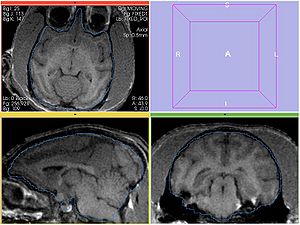

REGISTERED1